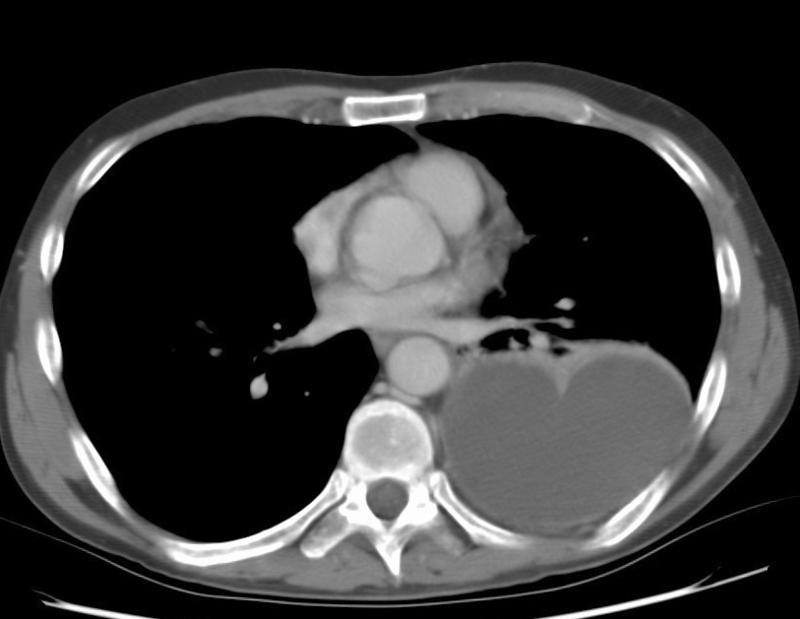

Gallery Pleural empyema 1c

empyema 1c